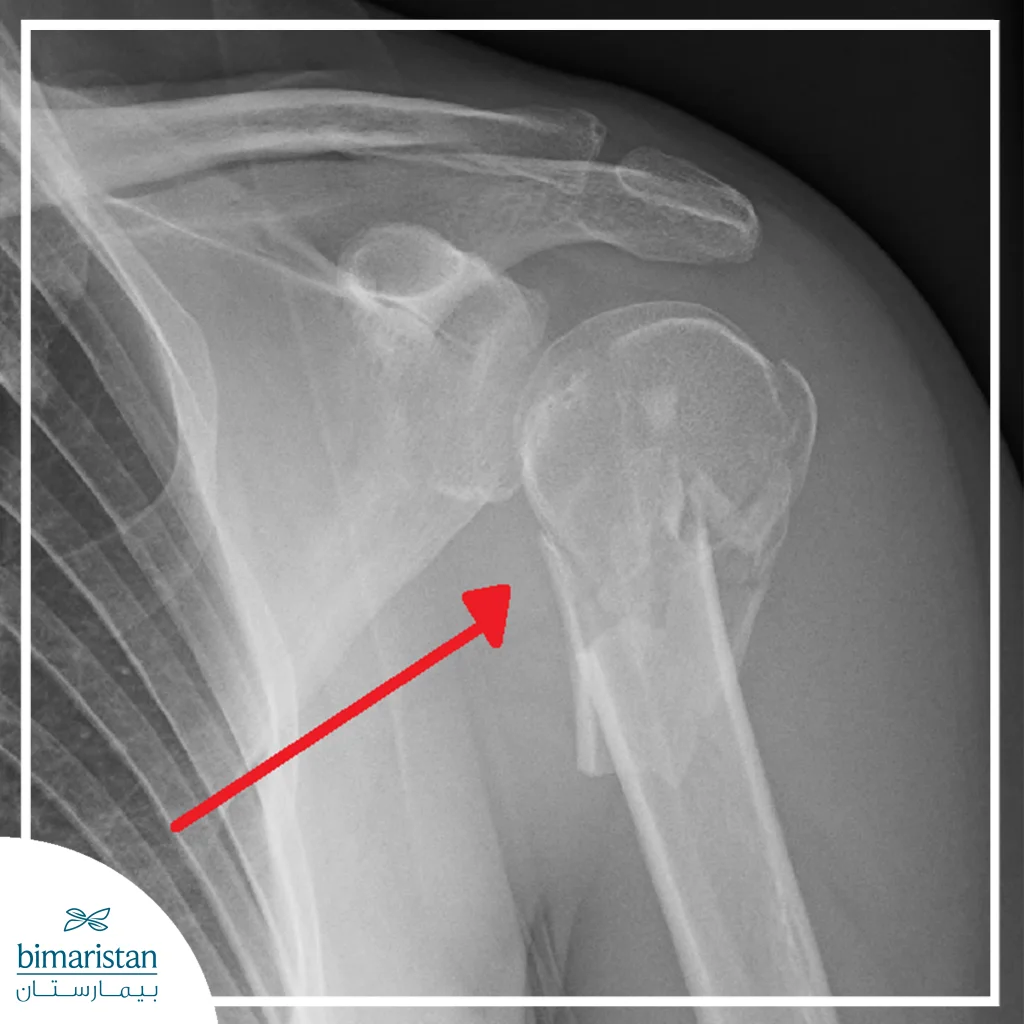

الأشعة السينية

تعتبر الأشعة السينية الطريقة الأكثر شيوعاً لتشخيص كسور الكتف، حيث تُظهر العظام بشكل واضح وتكشف عن مكان الكسر ونوعه (بسيط أو معقد)، تساعد الصور الشعاعية الأطباء على تحديد مدى انزياح العظام، وتقدير الحاجة لتثبيت الكسر جراحياً أو علاج تحفظي.